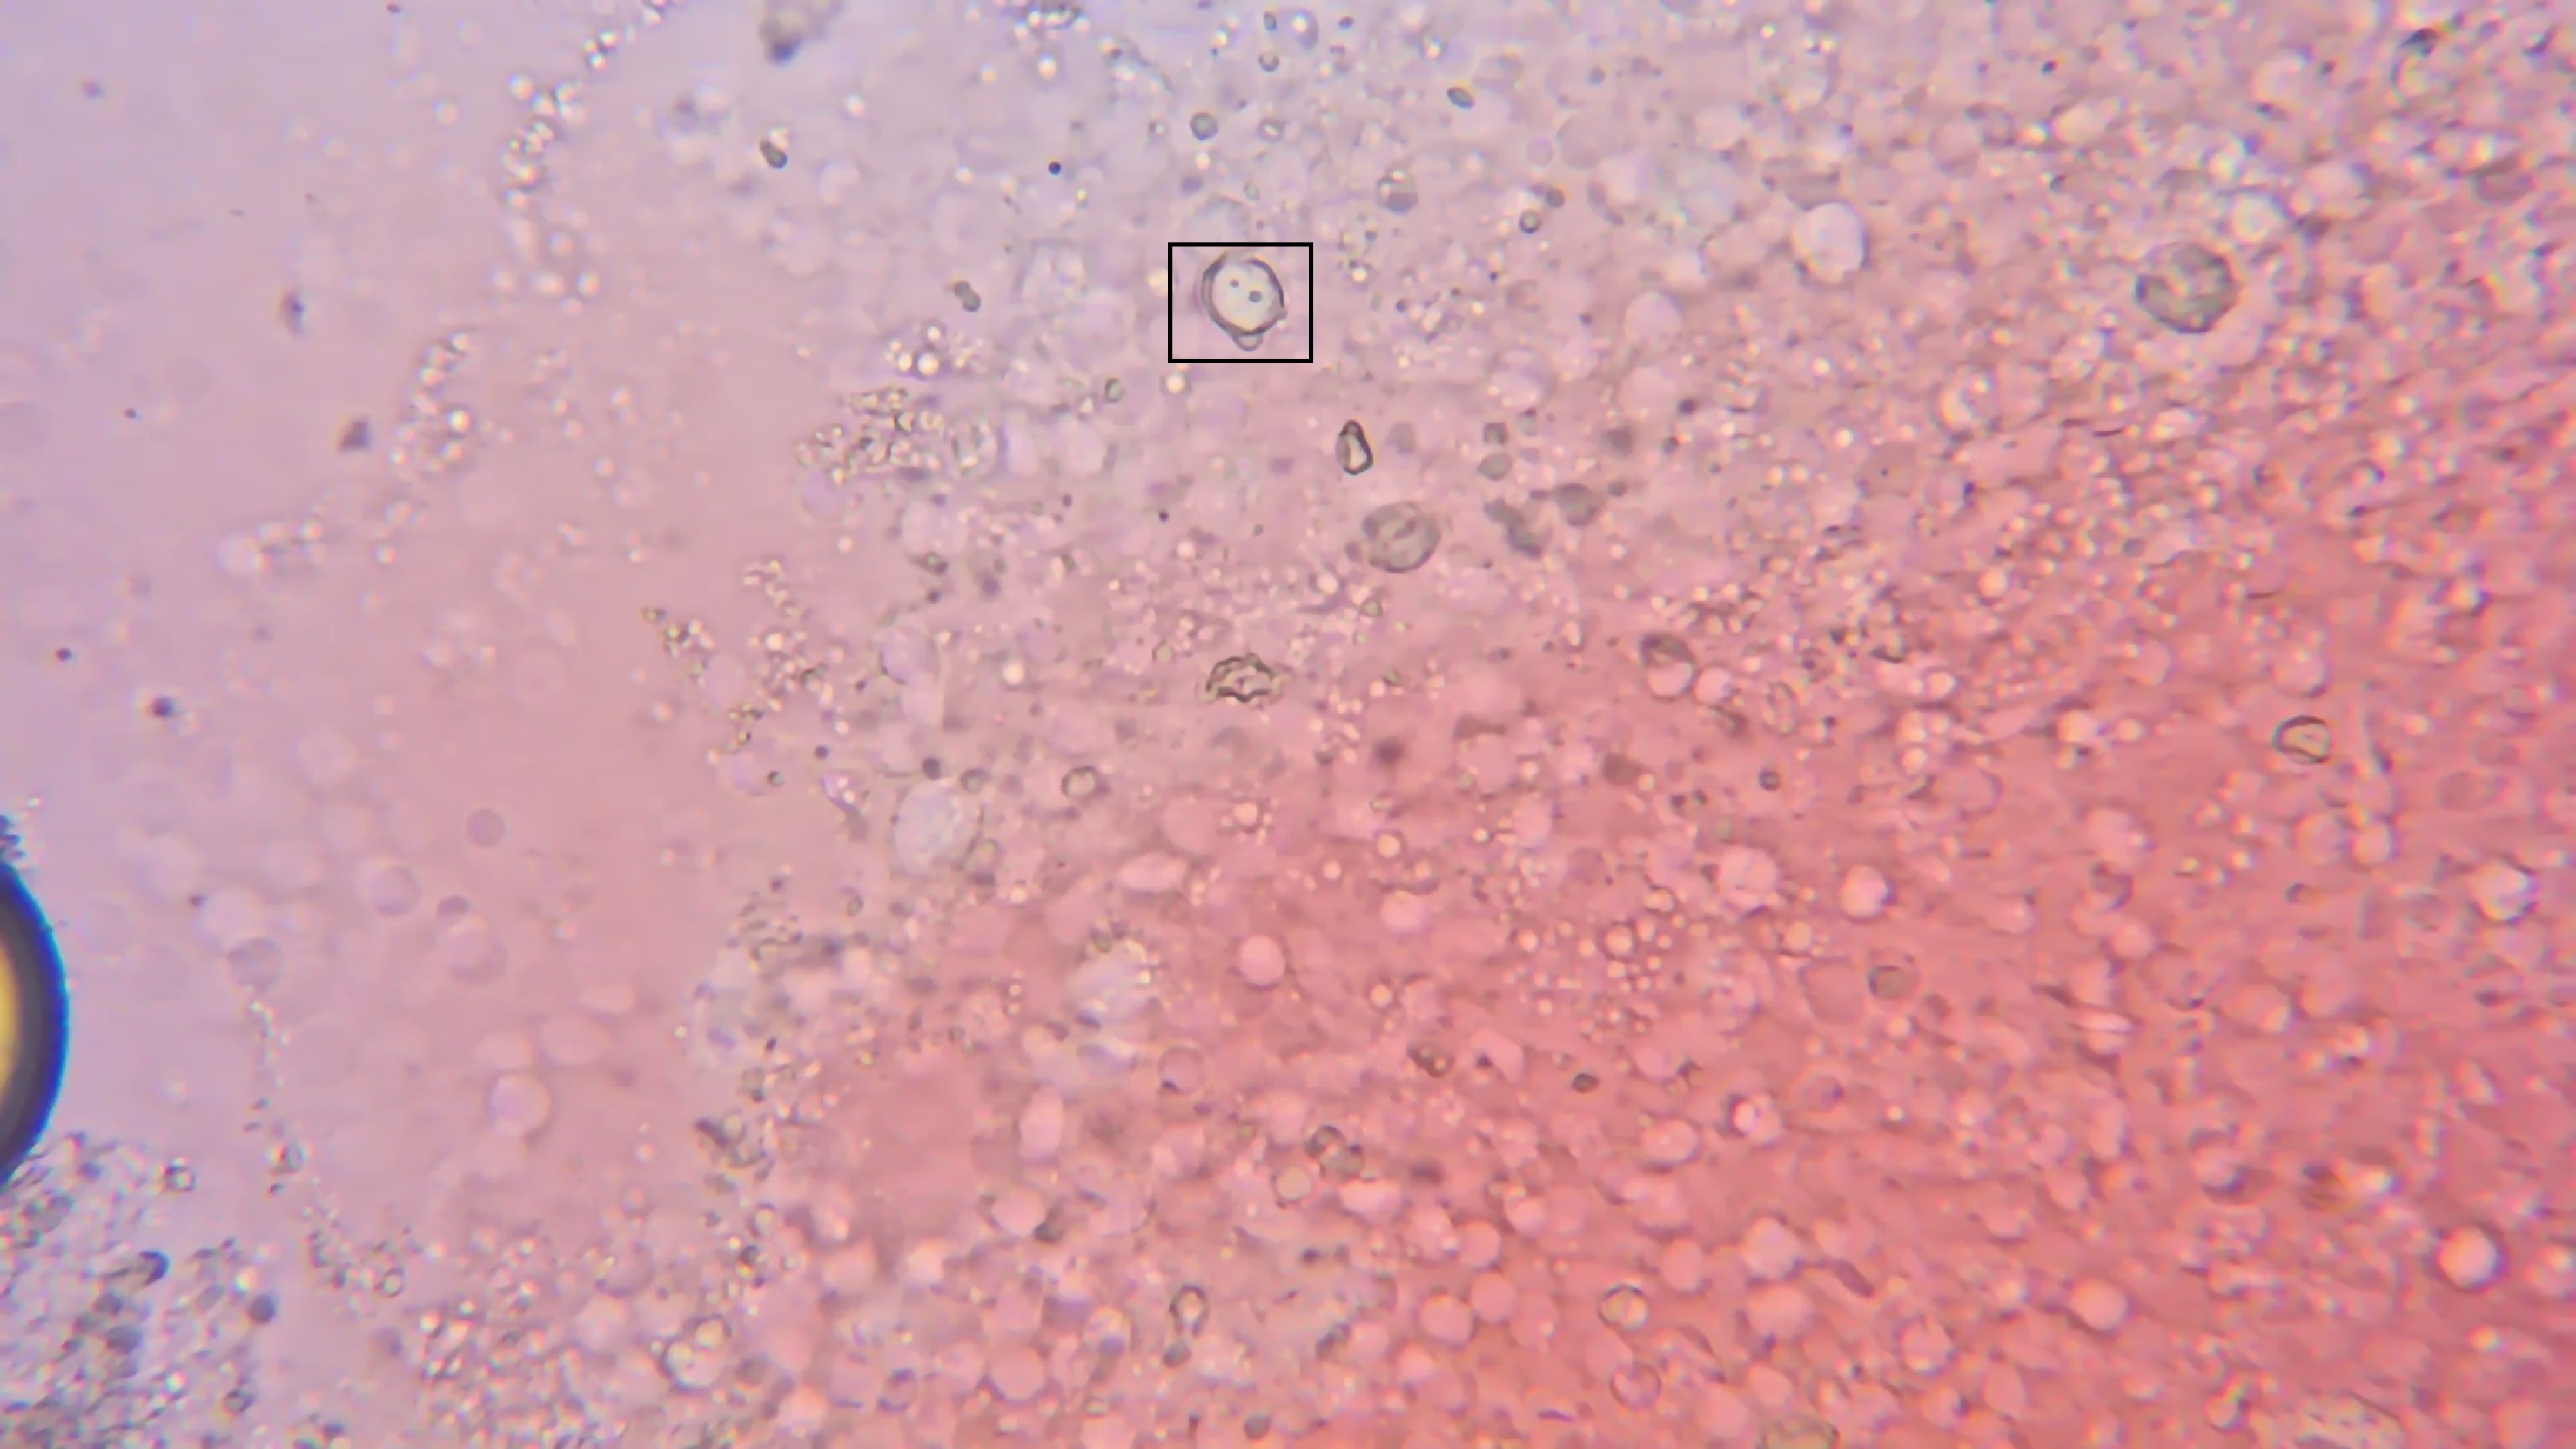

自身血液:

黑框内有一个白细胞。

这是未凝固的血液在显微镜下流动。